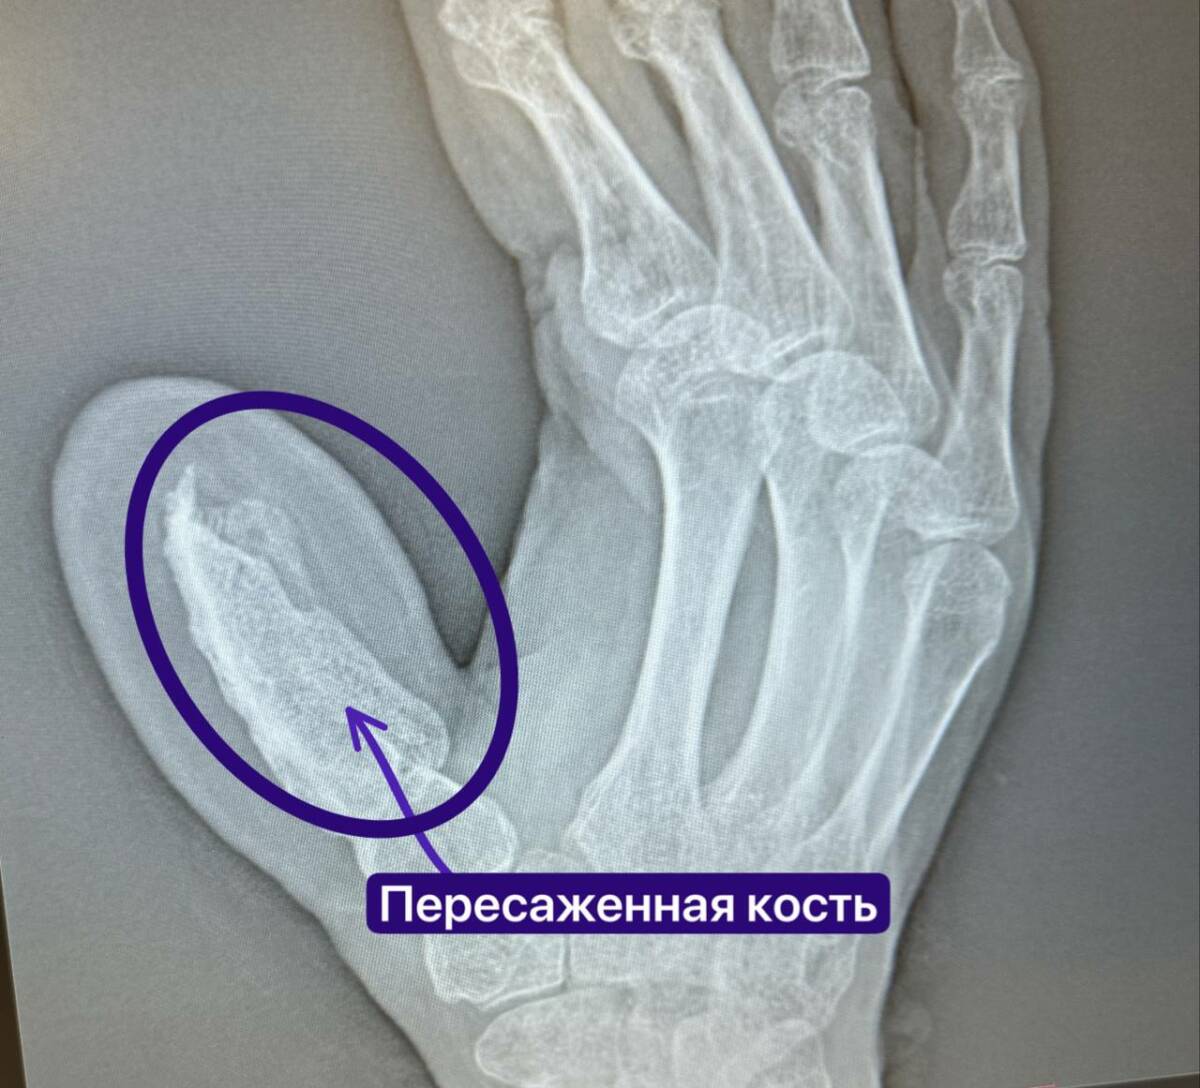

Беренче этапта хирурглар пациентның янбаш сөягеннән 5 сантиметр озынлыктагы сөяк кисәген һәм кан белән тәэмин итүче артерияне күчереп утыртканнар. Бармак өлешенә кан килсен өчен, кулын вакытлыча корсакка теккәннәр. Операция 4 сәгать дәвам иткән. Аны микрохирурглар Руслан Тельманович Радьков һәм Эльвира Рәфыйковна Кадыйрова башкарган.

Киләсе бер ярым ай дәвамында ир-ат сөякнең үсеп, урынга җайлашуын көткән.

«Күп очракта пациентлар мондый операцияләргә ризалашмый, чөнки корсакка тегелгән кул белән йөрергә теләмиләр. Әмма башкача сөяк җайлаша алмый – кан килми икән, организм аны кабул итми. Без исә сөякне артерия белән бергә күчердек, шуңа күрә туклану җитәрлек булды. Гомумән, бармак үстерү буенча операцияләр һәрвакытта да килеп чыга дип булмый. Бу очракта барсы да уңышлы булды, яңа сөяк кул сөякләренә «кушылды»», – дип аңлата Руслан Радьков.